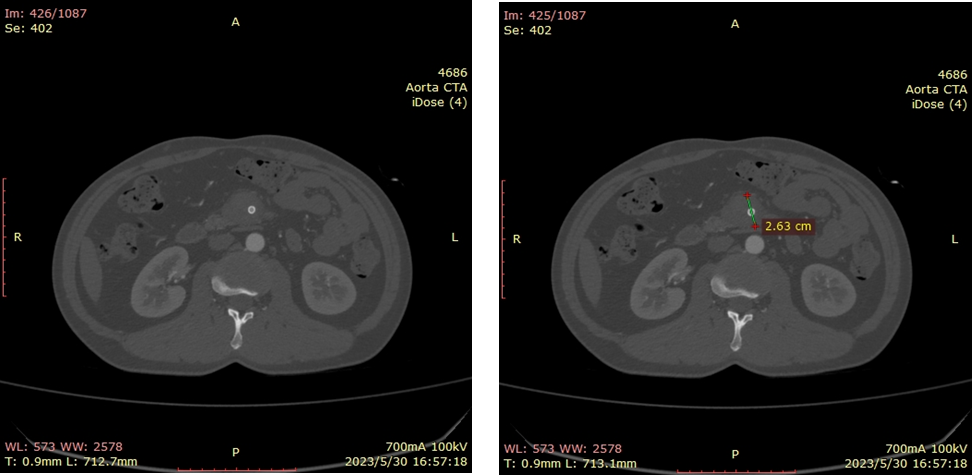

20230530CTA(术后1周):夹层动脉瘤隔绝完全

有的研究者把ISMAD影像学特征用于选择腔内支架治疗的标准,如在疑似肠道缺血的基础上,真腔狭窄80%或假腔动脉瘤直径>2cm;随访期间夹层动脉瘤直径>2cm或假腔溃疡型结构的扩大,这些作为腔内支架治疗的标准。但文献报道夹层动脉瘤破裂至今仅数例,临床随访症状缓解的病人,未见假腔快速扩张。